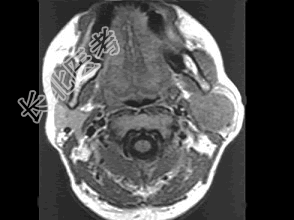

- [材料题] 女性,30岁,左侧腮腺无痛性包块5个月,无面瘫,触诊肿块质韧,表面光滑。大小约6×8厘米,B超示腮腺浅叶实性肿块 ,均质,包膜完整。患者相片及影像资料见下图。